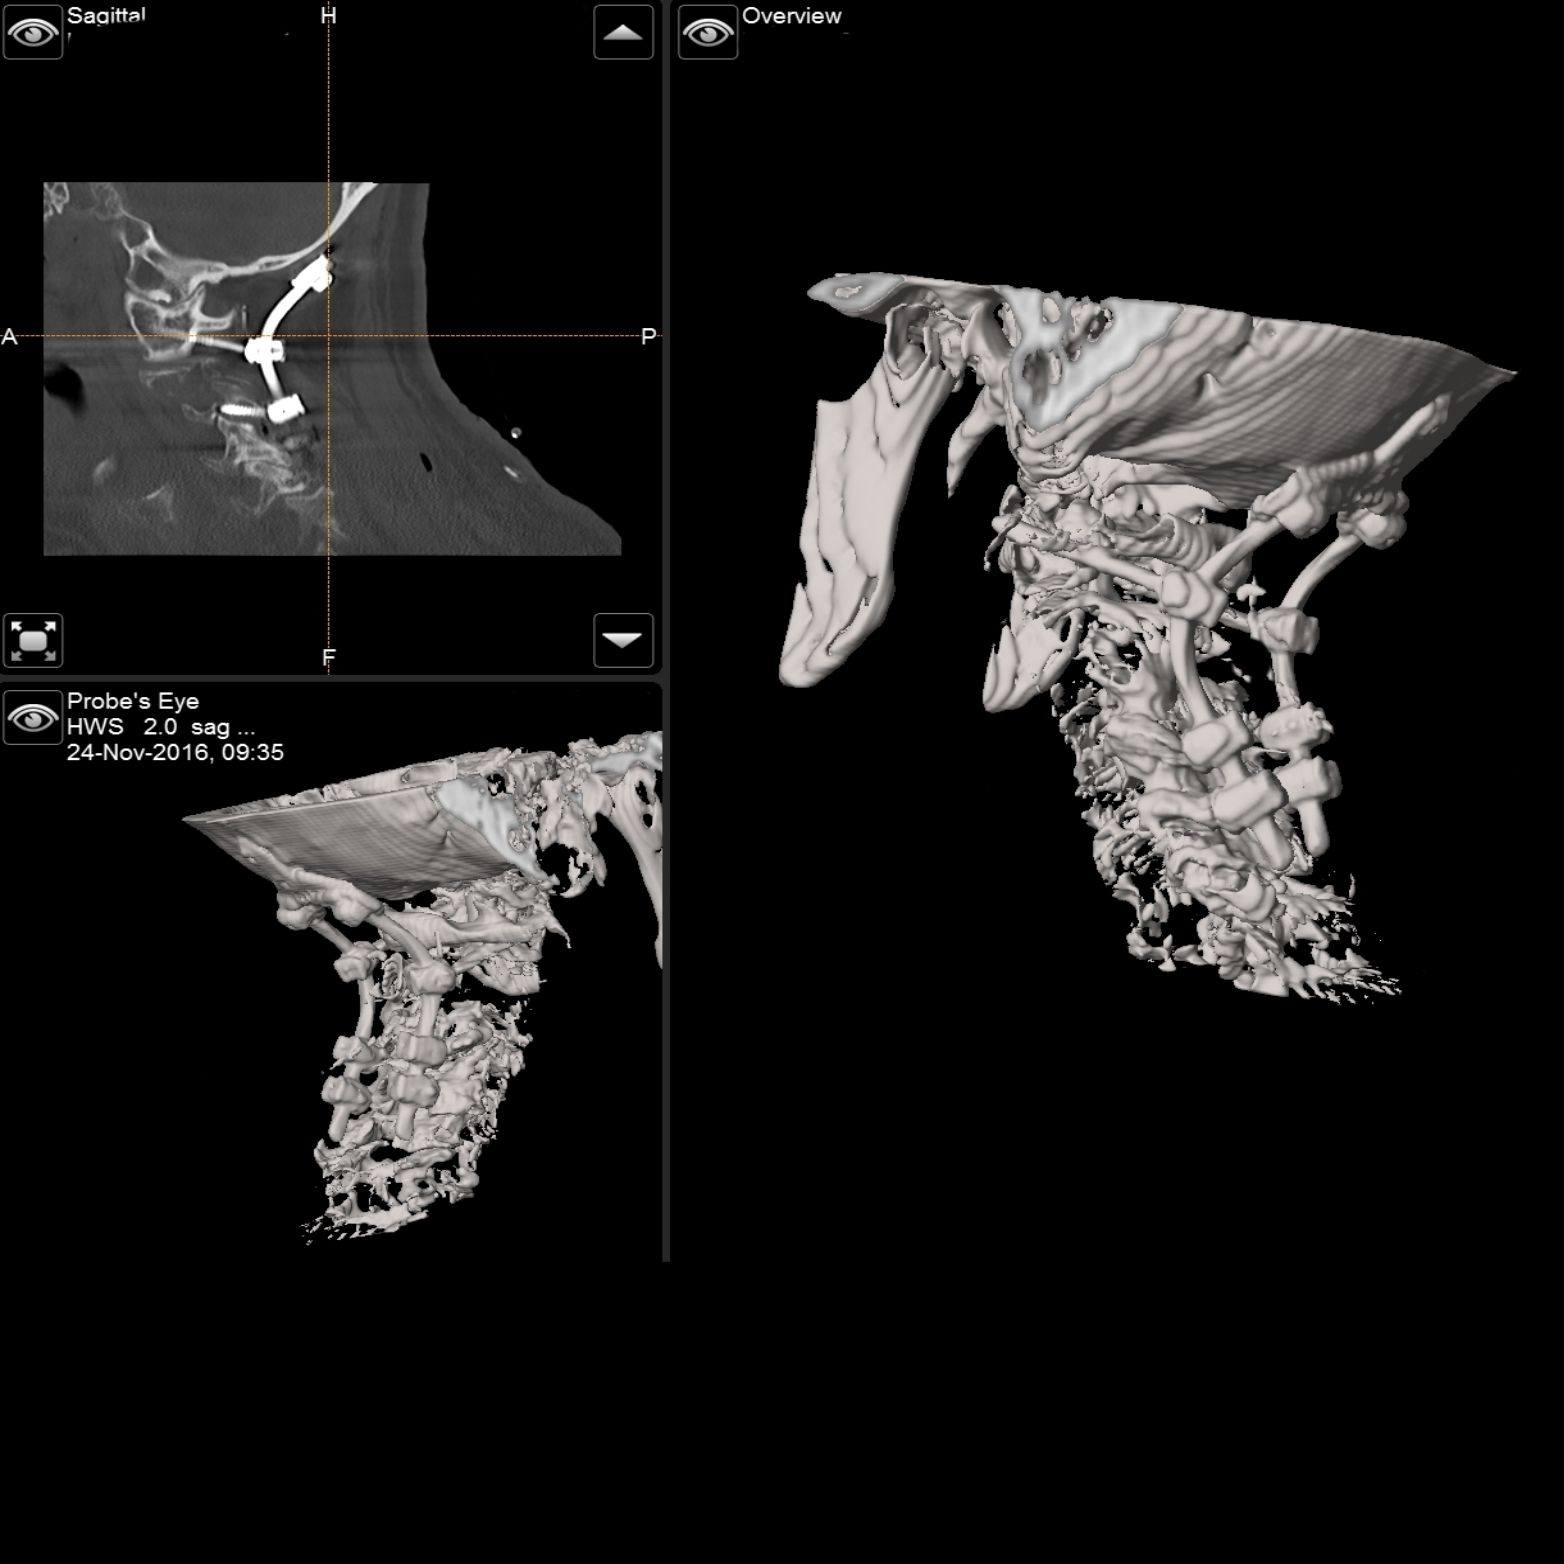

Intraoperativer Röntgen C-Bogen mit 3D Rekonstruktion

Intraoperativer Röntgen

C-Bogen mit

3D Rekonstruktion

Die Universitätsklinik Tübingen verfügt über hochmoderne mobile Bildgebungssysteme, darunter der robotisch geführte digitale Volumentomograph Loop-X der Firma Brainlab sowie ein mobiler 3D-C-Bogen der Firma Ziehm. Diese fortschrittlichen Systeme ermöglichen intraoperativ eine präzise 3D-Rekonstruktion des Kopfes oder der Wirbelsäule. Für die Kopf- und Wirbelsäulenchirurgie kann mithilfe dieser Technologien ein Navigationsdatensatz erstellt werden, der eine hochpräzise Navigation gewährleistet. So können beispielsweise Schrauben in der Wirbelsäule exakt platziert und kontrolliert oder Trajektorien für Zugangswege und Probenentnahmen im Kopf definiert werden.